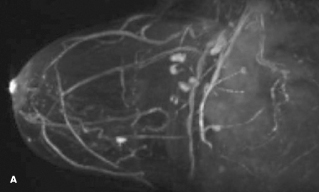

A diagnostic mammogram and an ultrasound scan were normal. An MRI scan of the breast revealed an abnormally enhancing 1-cm lesion within the right upper-inner quadrant (A and B). MRI-guided needle biopsy was performed; pathology results demonstrated a glomus tumor (C and D).